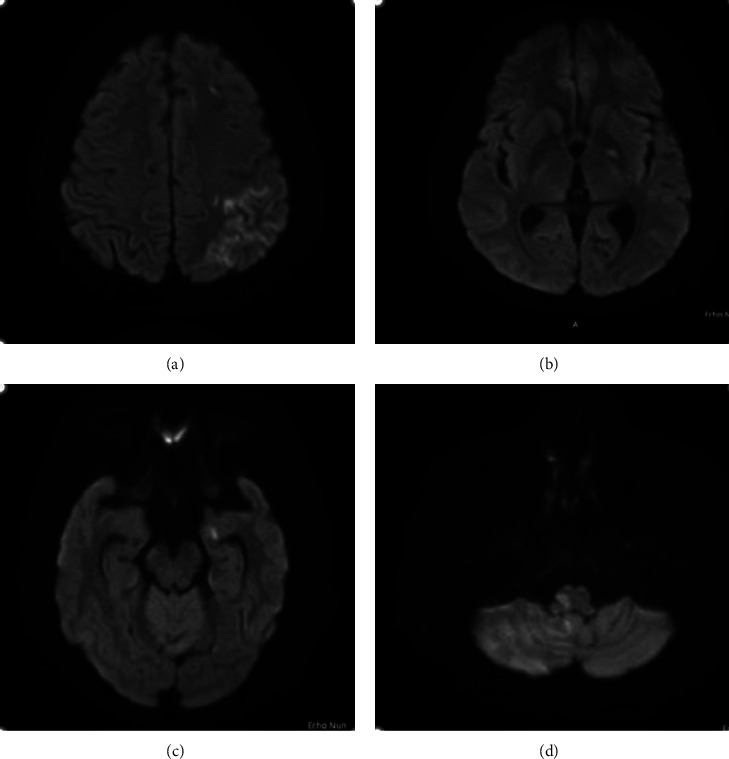

由副丝状念珠菌引起的人工瓣膜心内膜炎(PVE)导致的栓塞性中风是一种罕见的严重并发症。成功的治疗需要内科和外科相结合的方法。我们介绍了一个在诊断和治疗念珠菌性 PVE 时充满复杂性的病例,强调了多学科方法的重要性。一名50岁的男性因眩晕和低烧到急诊科就诊,被发现患有小脑卒中,很可能是心源性栓塞引起的,患者有未控制的糖尿病史和双人工瓣膜病史。诊断具有挑战性,需要进行经食道超声心动图(TEE)检查,结果显示二尖瓣假体上附着两个植被。治疗包括抗真菌治疗,但手术因经济问题而受阻。由于真菌血症持续存在,患者被考虑使用 AngioVac 植被抽吸系统。最终,手术没有进行,患者出院时计划接受长期抑制性抗真菌治疗。

Embolic stroke due to prosthetic valve endocarditis (PVE) caused by Candida parapsilosis is a rare and serious complication. Successful management requires a combination of medical and surgical approaches. We present a case full of complexities in diagnosing and managing Candida PVE, emphasizing the importance of a multidisciplinary approach. A 50 year-old male presented to the emergency department with vertigo and low-grade fever and was found to have cerebellar stroke likely from the cardioembolic origin, and the patient had a history of uncontrolled diabetes and double prosthetic valves. The diagnosis was challenging and required transesophageal echocardiography (TEE) which showed two vegetations attached to the mitral valve prosthesis. The management involved antifungal therapy, but surgery was hindered by financial issues. The patient was considered for the AngioVac vegetation aspiration system due to persistent fungemia. Eventually, surgery was not performed, and the patient was discharged with a plan for long-term suppressive antifungal therapy.